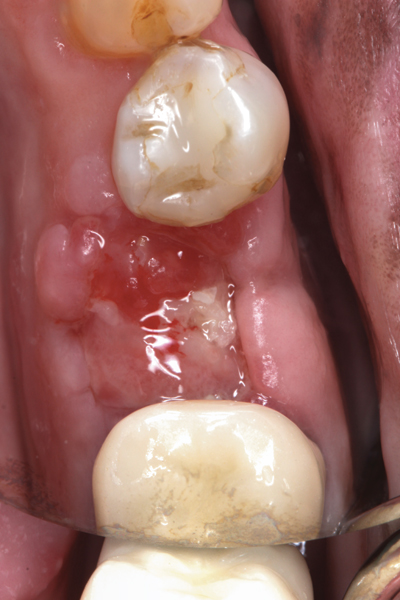

Fig 8. At 4 weeks postoperative, the barrier has been removed exposing osteoid tissue.

Figure 8

Fig 9. At 8 weeks postoperative, the ridge was keratinized.

Figure 9

Fig 10. At 3 months postoperative, the flap was elevated demonstrating a restored buccal plate of bone.

Figure 10

Fig 11. An implant was placed in regenerated bone.

Figure 11